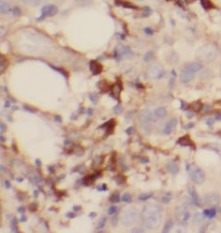

Immunohistochemistry of paraffin-embedded human breast cancer using FNab03661(GRP75 antibody) at dilution of 1:100